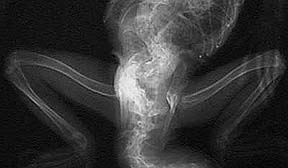

The pelvis on this iguana is too deformed for eggs to pass. This pet has a severe form of iguana bone disease called NSHP.

An egg bound iguana usually has a distended abdomen (technically the coelomic cavity). Depending on the number of eggs and their level of calcification these eggs can actually be felt when the abdomen is palpated. Radiography is used commonly to verify the diagnosis.

Can you visualize the numerous round and subtle swellings in the coelomic cavity (reptile equivalent of the abdomen) of this female iguana?